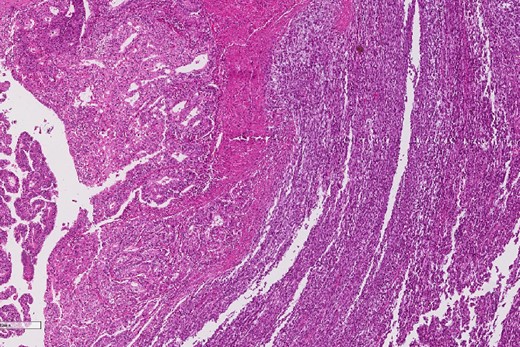

A review of the previously resected esophageal tumor revealed the presence of both epithelial and sarcomatous components. The epithelial component was composed of moderately to poorly differentiated adenocarcinoma, while the sarcomatous component showed hyperchromatic round to spindle cells with scant cytoplasm and frequent mitoses (Figs 3–6). The intrathoracic tumor showed a similar morphology as the sarcomatous component of the esophageal tumor, with focal rhabdomyoblastic differentiation (Fig. 7). The latter was strongly positive for desmin, myogenin, and MyoD1 and was focally positive for synoplastin, CD56, CD 10, and FL1.

The sarcomatous component of the esophageal tumor is formed of hyperchromatic round to spindle cells with scant cytoplasm and frequent mitoses.